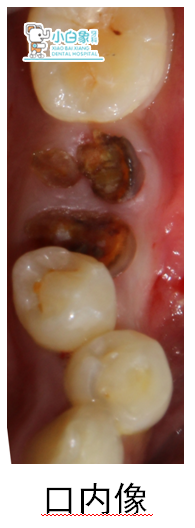

检查:口内查:36牙根平齐牙龈,叩(-),牙龈无红肿。

诊断:36残根。